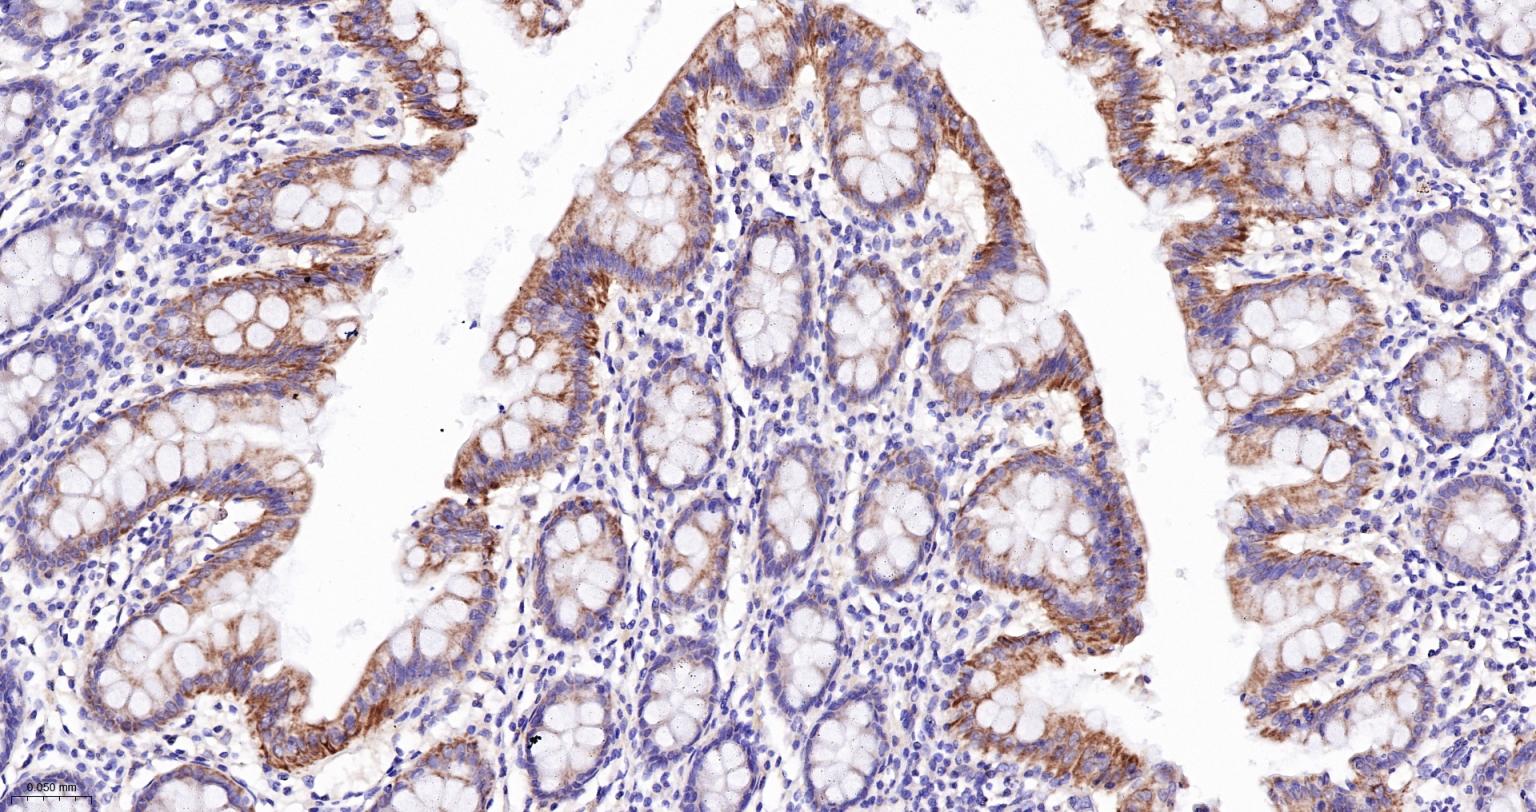

Paraformaldehyde-fixed, paraffin embedded Human Colon; Antigen retrieval by boiling in sodium citrate buffer (pH6.0) for 15 min; Antibody incubation with Bak Monoclonal Antibody, Unconjugated(bsm-61174R) at 1:200 overnight at 4°C, followed by conjugation to the SP Kit (Rabbit, SP-0023) and DAB (C-0010) staining.